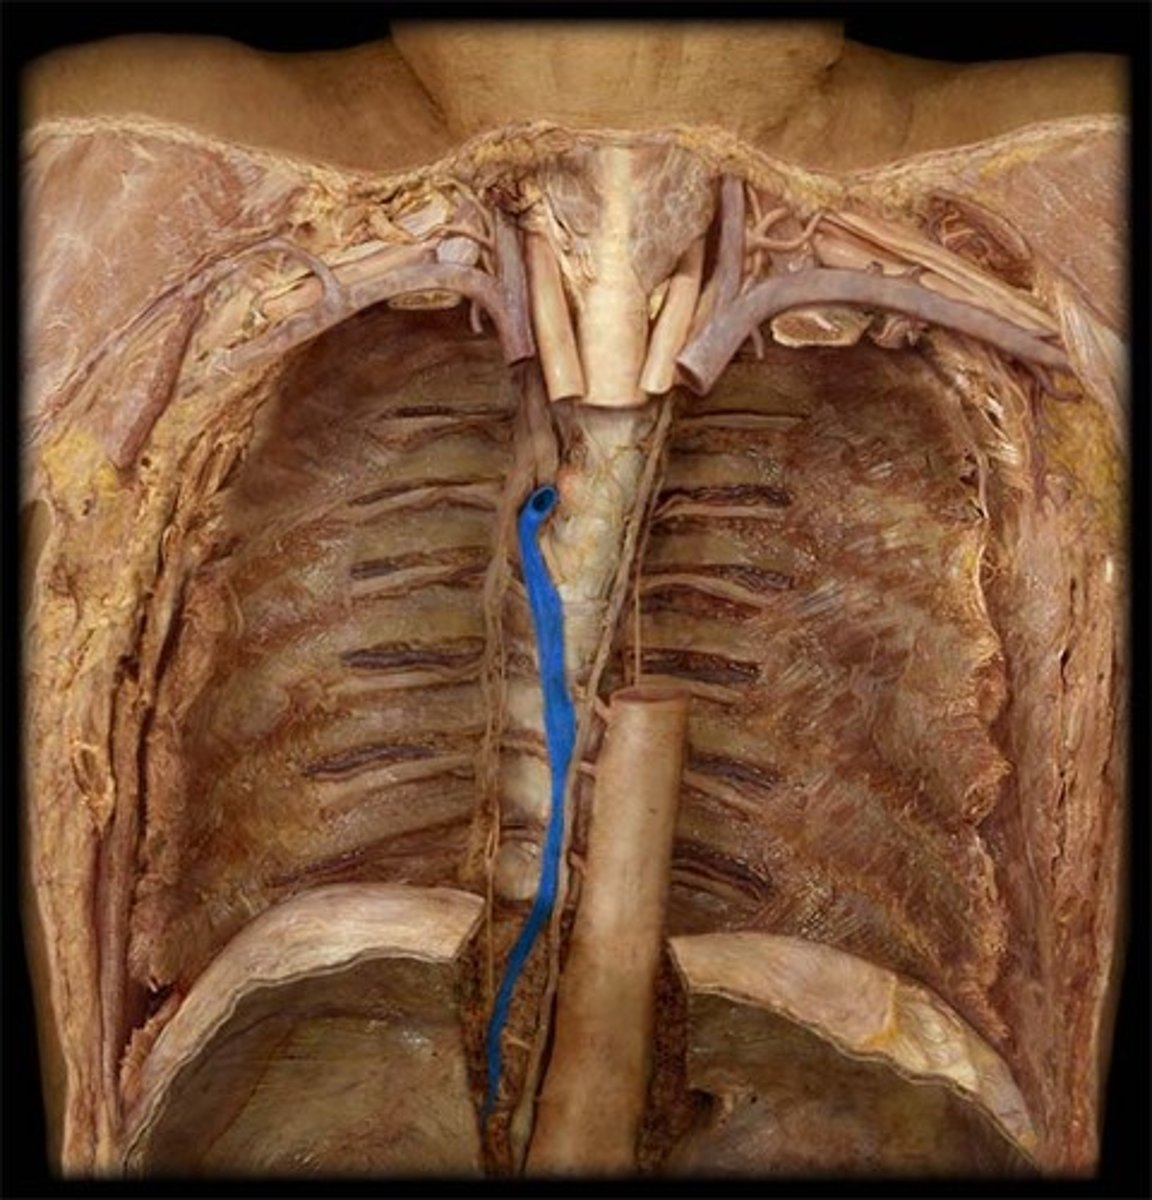

azygos vein

thoracic duct